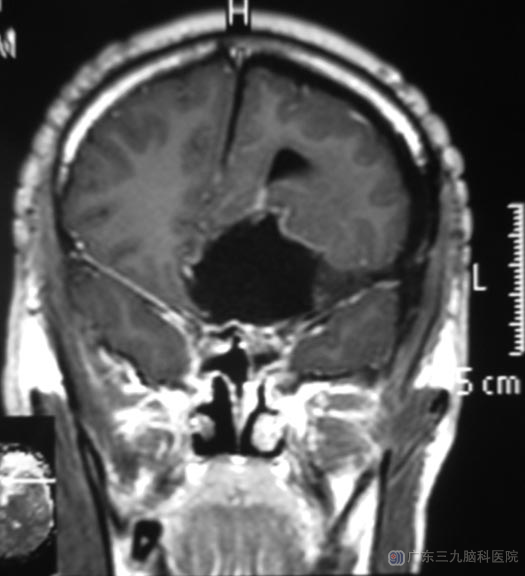

完善检查后,鲁明主任主刀,在全麻下行冠状切开左额入路前颅窝底肿瘤切除术。术中见肿瘤呈灰褐色,位于前颅窝底,质中,显微镜下分块全切,术中视神经、颈内动脉及其分支保护完好。术后,嗅觉较术前好转。病理结果:恶性黑色素瘤。

▲术后MR